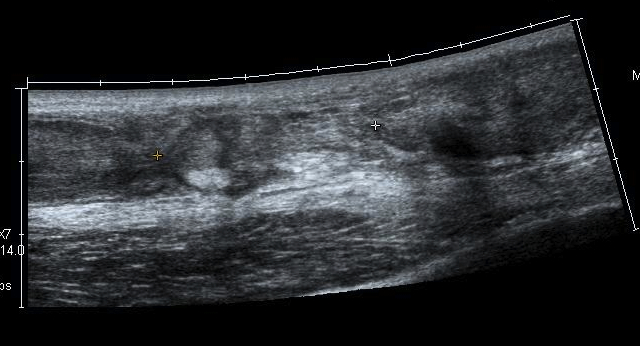

Ultrasound

Diagnose rupture and check reduction of tendon ends with plantarflexion

Aminlari et al J Emerg Med 2021

- systematic review

- ultrasound 95% sensitive and 99% specific for complete rupture